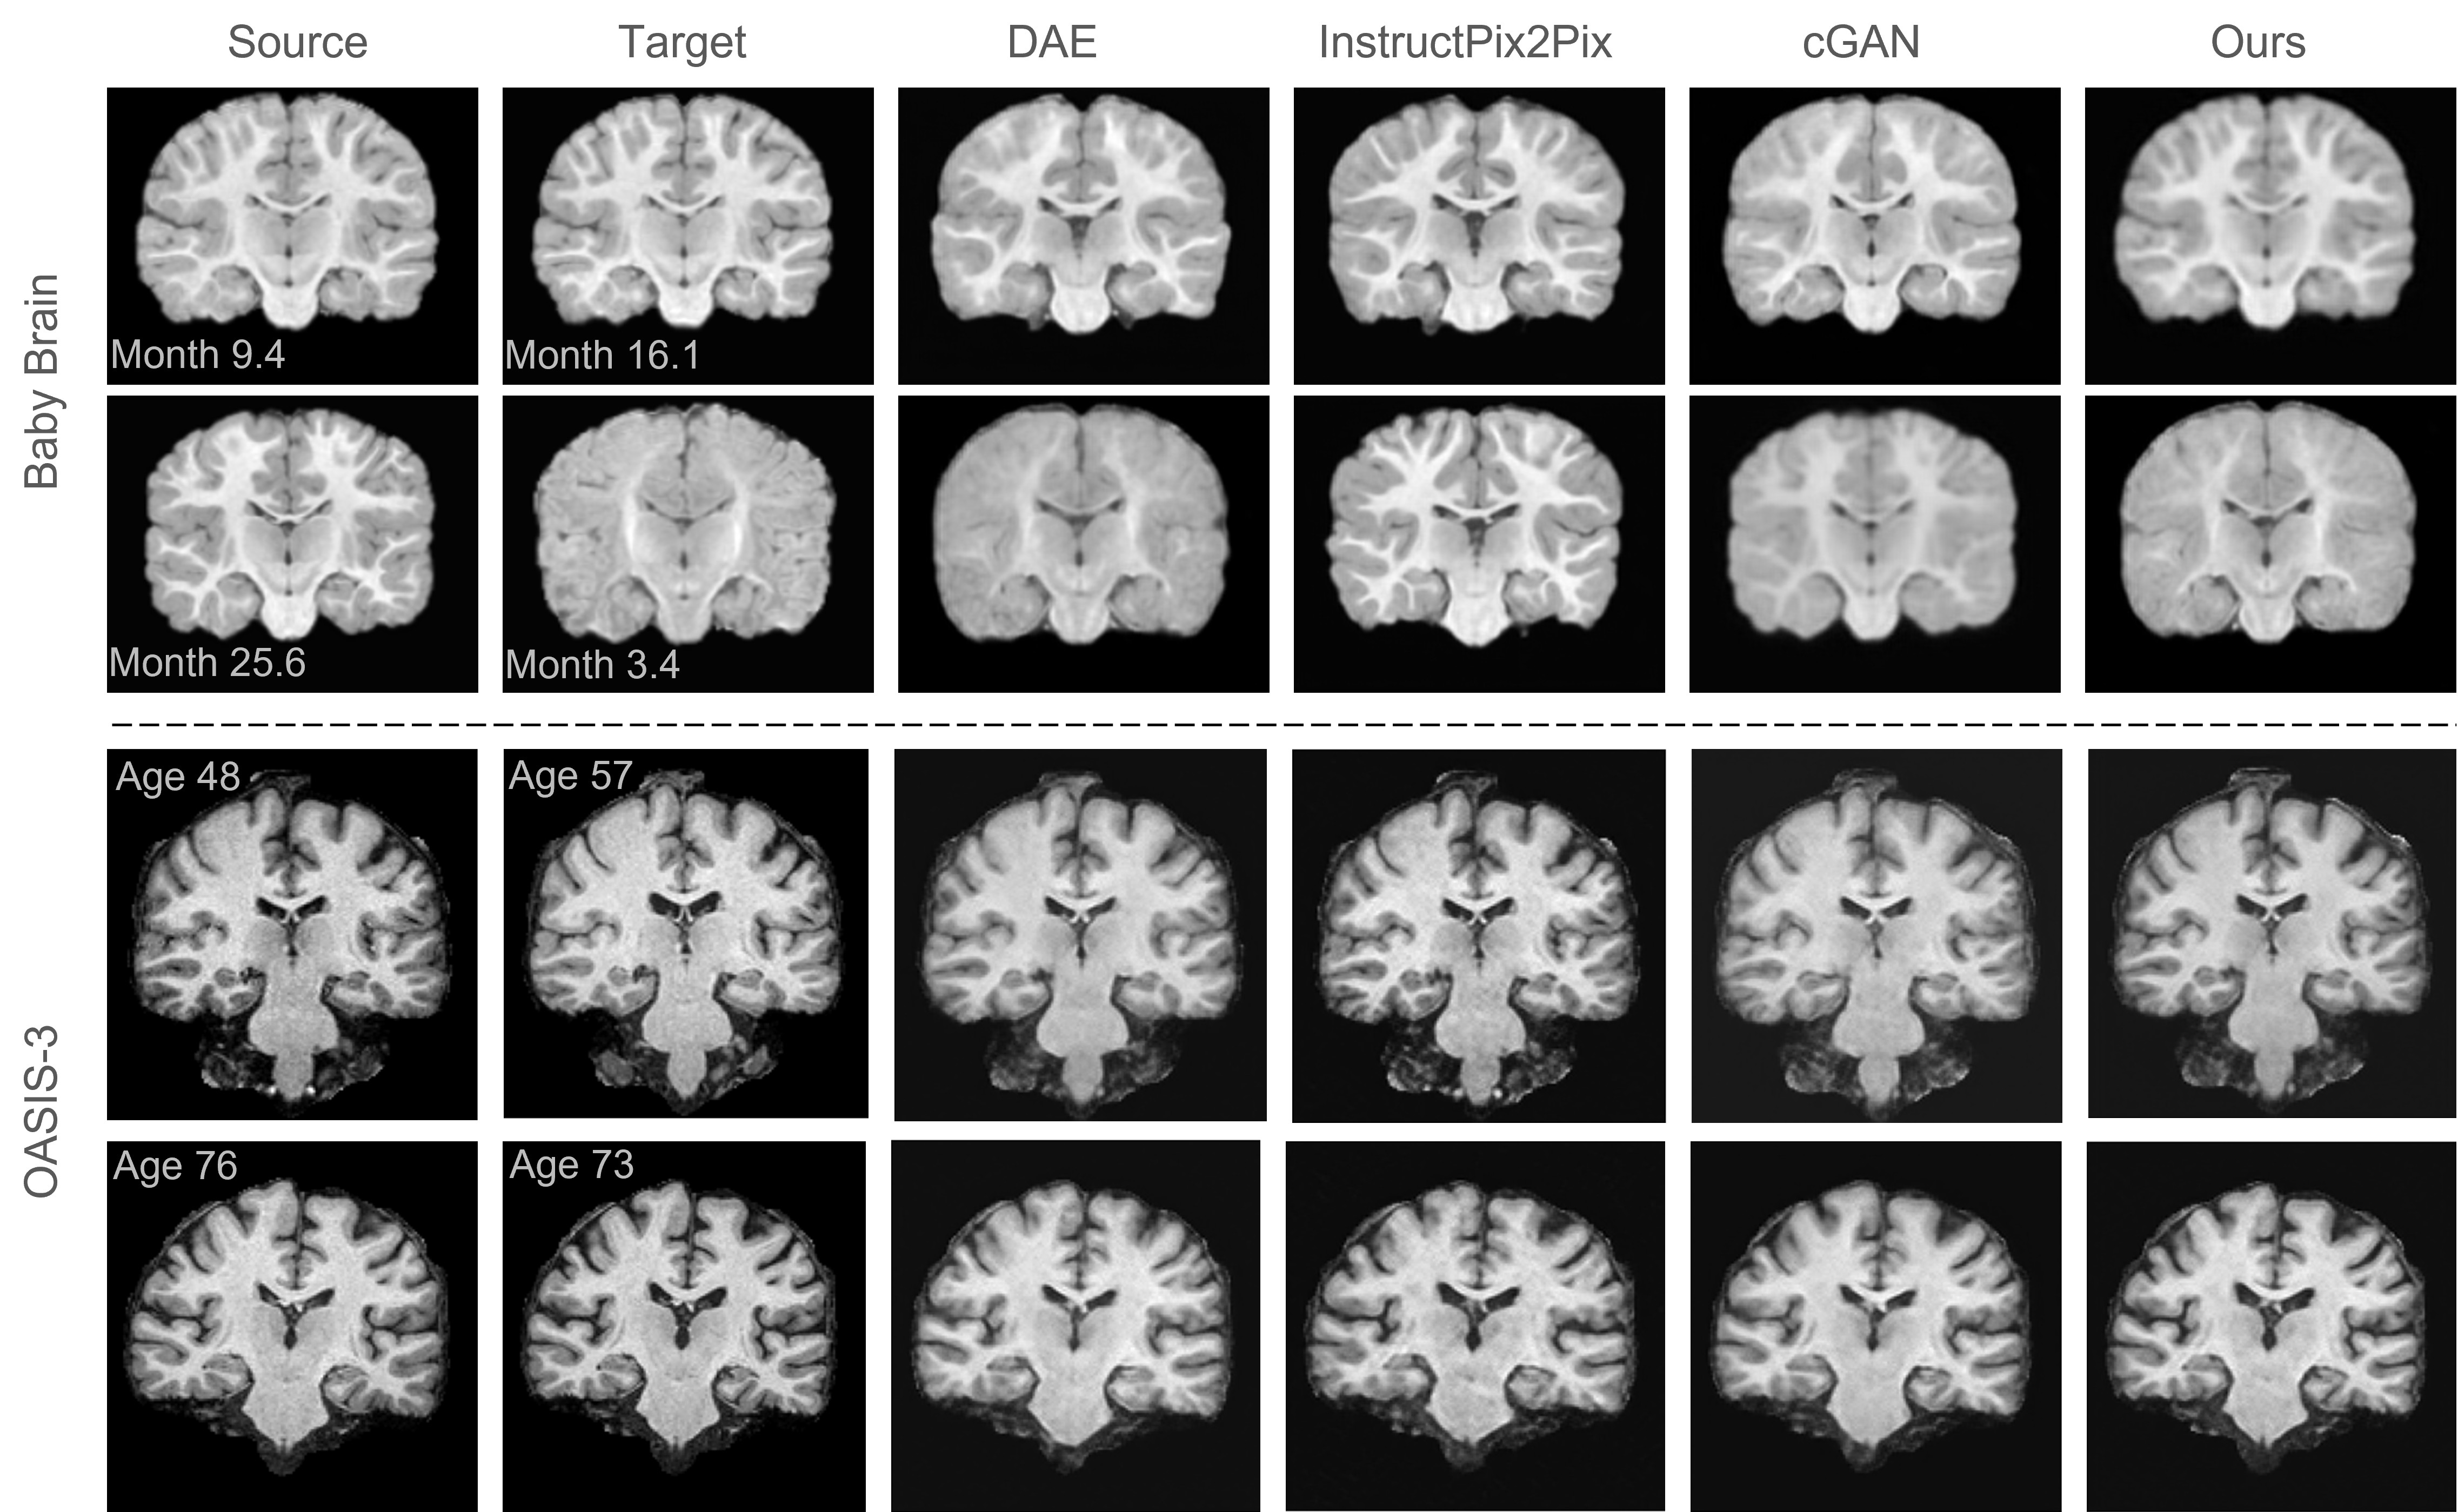

Refer to caption

Figure 2: Visualization of baseline comparison on the Baby Brain and OASIS-3 datasets. The brain images are generated by different models based on the source images, which are expected to align with the target images. In the first row, the source and target are similar in age, resulting in subtle yet discernible longitudinal changes. Our method preserves the identity more effectively compared to other non-identity-preserving baselines.

Tab. 1 presents a performance comparison of IP-LDM against SOTA methods on the OASIS-3 and Baby Brain datasets. On the OASIS-3 dataset, IP-LDM achieves the highest SSIM 0.949 and PSNR 35.15, indicating superior structural similarity and image fidelity. Additionally, IP-LDM records the lowest FID 4.733 and RMSE 1.868, reflecting high-quality and accurate image generation. The highest ARI 0.99 further underscores IP-LDM’s capability in maintaining identity preservation. Similarly, on the IBIS dataset, IP-LDM outperforms other methods with the highest SSIM 0.674 and PSNR 32.989, and the lowest FID 4.984 and RMSE 8.996, demonstrating its robustness in producing realistic and precise brain images during age transformation. Notably, the GAN-based method (cGAN) performs better on the Baby Brain dataset compared to the OASIS-3 dataset. We attribute this difference to the inherent characteristics of the datasets. Please refer to App. D for further details.

The visualization shown in Fig. 2 further underscores the superior performance of IP-LDM. The figure displays brain images generated by different methods across the Baby Brain and OASIS-3 datasets, generating target images based on source images. For both datasets, IP-LDM produces images that closely resemble the target images, maintaining fine structural details and anatomical accuracy. The generated images exhibit clear ventricles and well-preserved brain structures, indicative of successful identity preservation and realistic aging transformation. In contrast, images generated by cGAN and DAE display noticeable artifacts and structural inconsistencies. cGAN, while producing visually realistic images, often fails to maintain finer identity-specific details, leading to less accurate age transformations. DAE struggles with both realism and structural integrity, showing blurred and less detailed images. InstructPix2Pix performs better than cGAN and DAE but still falls short of the accuracy and fidelity demonstrated by IP-LDM, especially in maintaining subtle geometric variations and anatomical features.